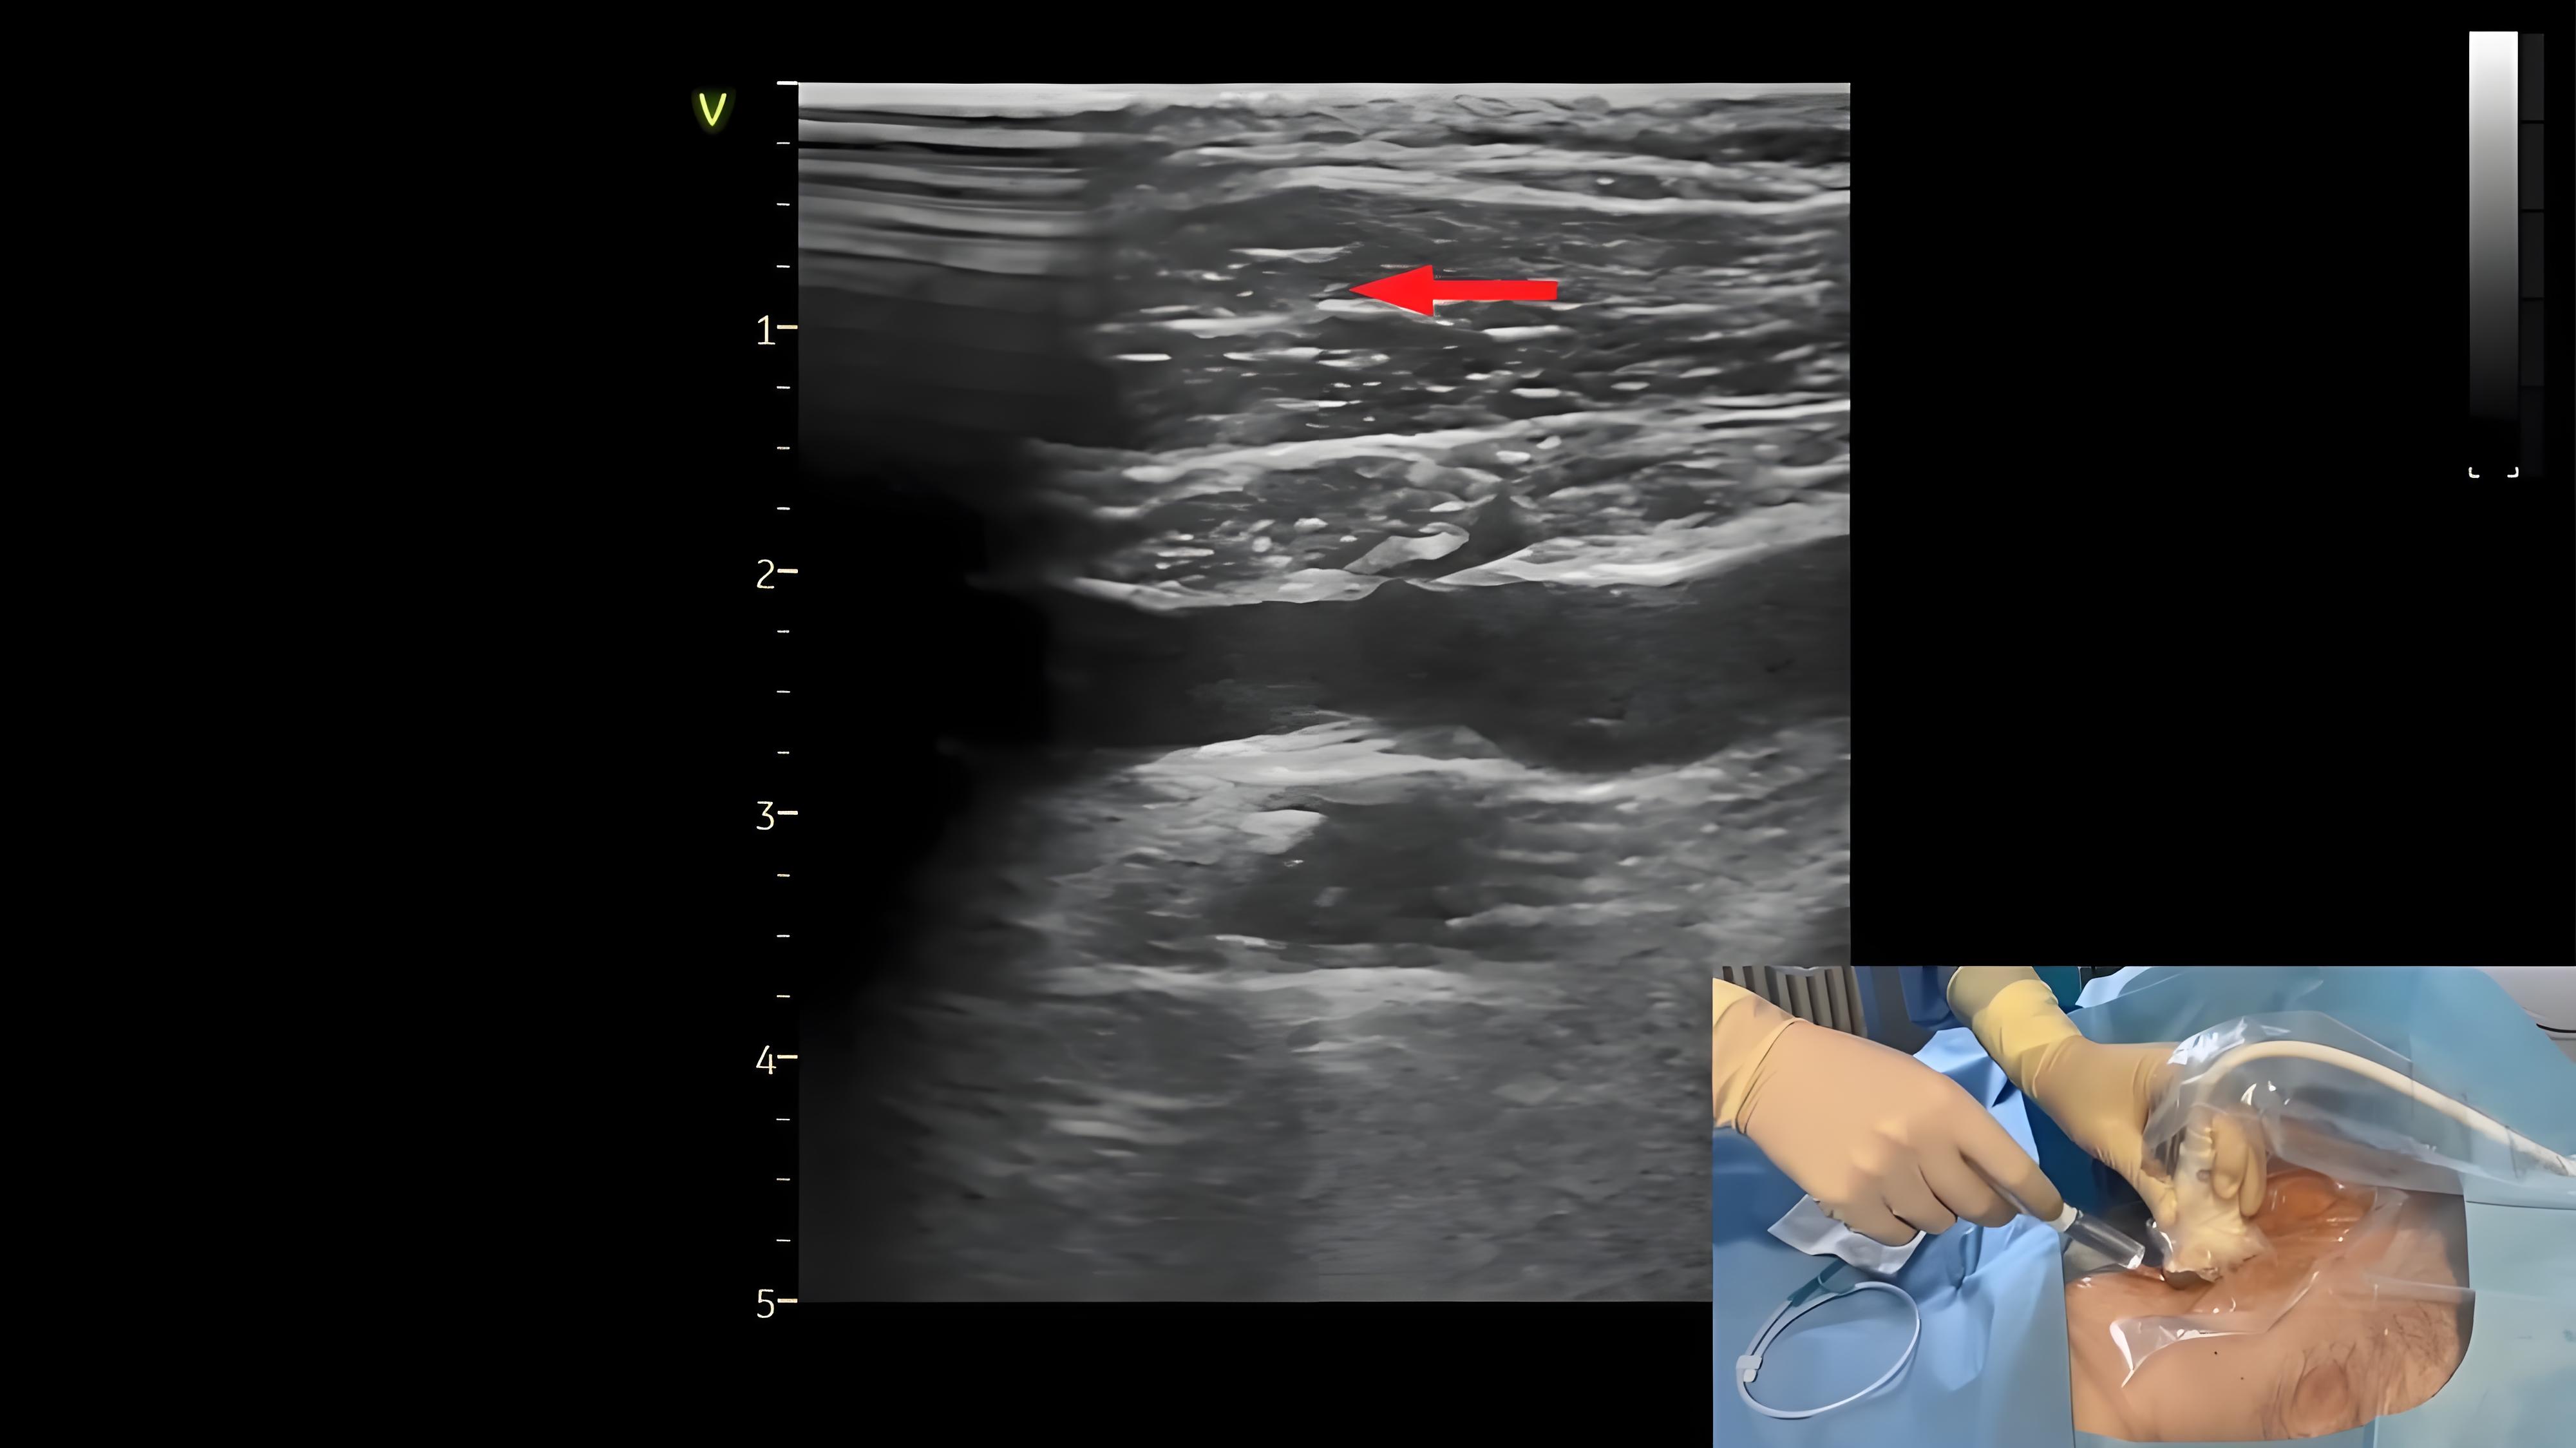

超声实时引导下颈内静脉穿刺置管

362 #颈内静脉穿刺